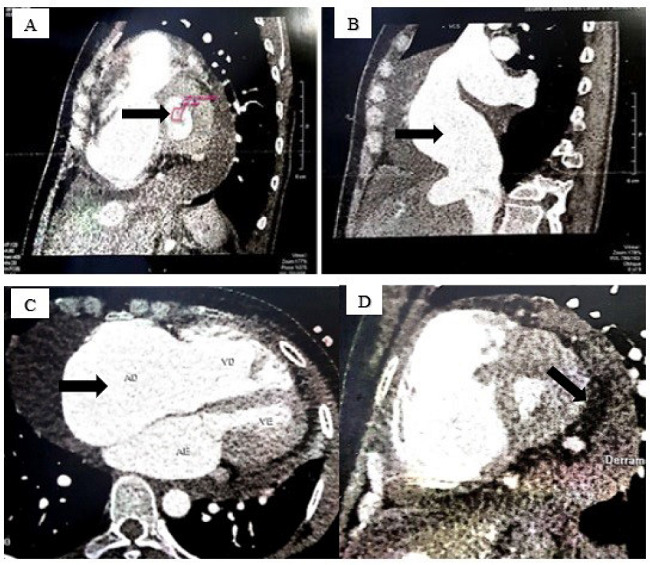

A coronary angiotomography was requested to investigate the possibility of associated coronary artery disease, which demonstrated pericardial effusion, a discrete myocardial bridge in the middle third of the anterior descending artery with no luminal reduction, thickened mitral valve leaflets and reduced opening (estimated valve area at 0.6 cm2), and the presence of ground-glass images in both lung fields (Figure 3).